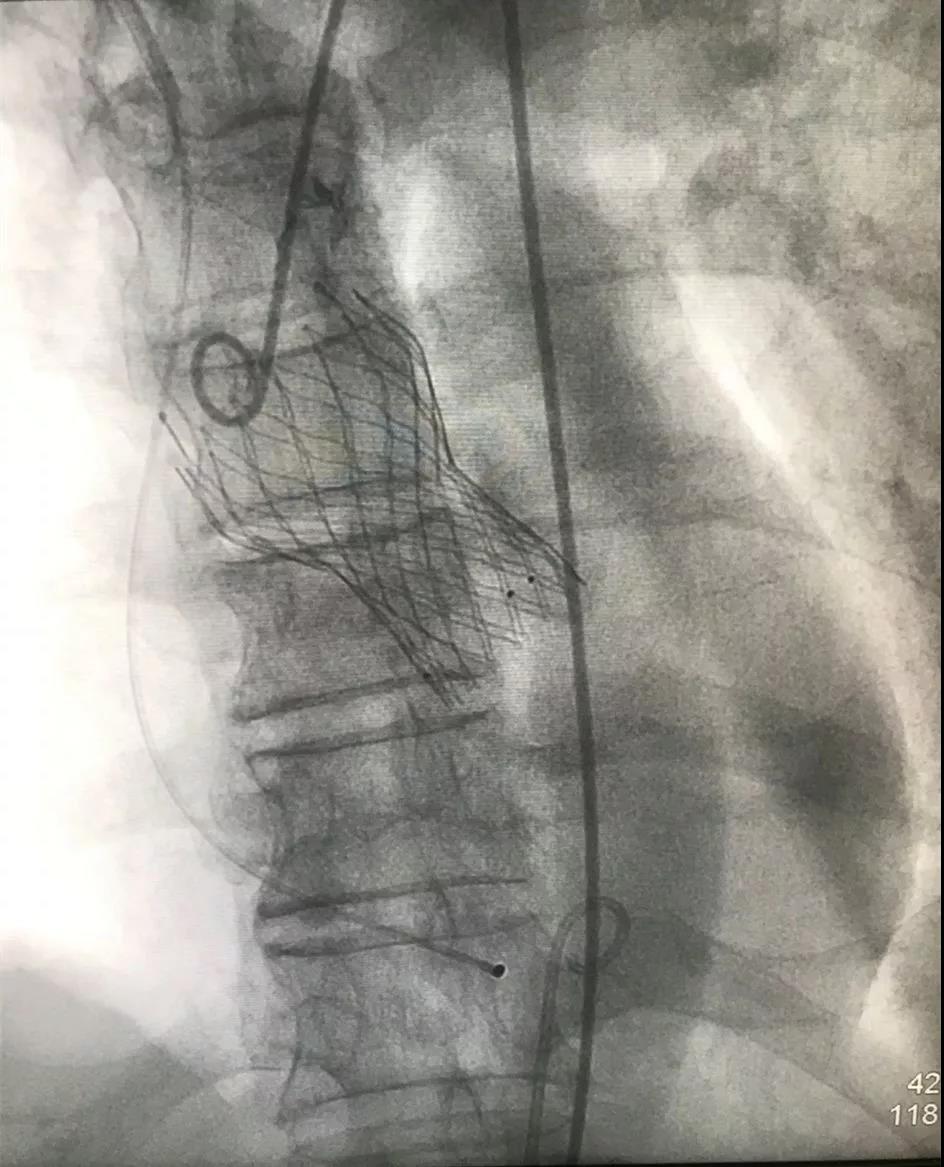

▲启明Venus-A瓣膜植入术后

郭延松副院长、陈新敬副主任介绍,经导管主动瓣植入术是国际先进、国内领先的技术,通过小小的导管,无需胸部切口,仅需通过股动脉穿刺将自膨式瓣膜置入主动脉瓣位,替代病变的自身主动脉瓣,恢复其应有的开闭功能。手术无需体外循环,最大限度地减少了创伤,减小手术风险,尤其是经股动脉途径的经导管主动瓣植入术手避免了传统的开胸、体外循环和心脏停跳,因此对于不能耐受传统心脏手术的病人尤其适用。我院成功开展首例经股动脉途径导管主动瓣植入术,是我科治疗心脏瓣膜病方式的一项里程碑式改变,标志着我科跻身于国内少数可行该手术医院的行列,为广大失去手术机会的严重主动脉瓣狭窄患者带来了新的希望。